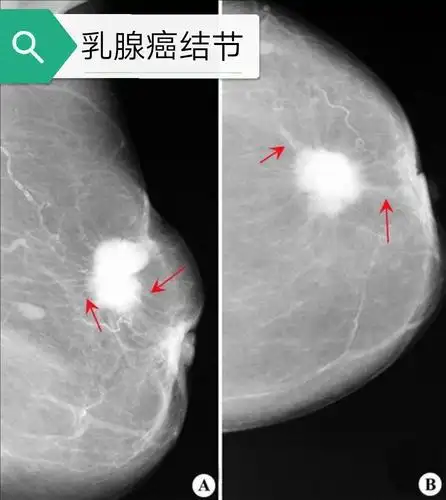

乳腺钼靶片